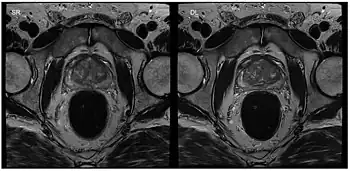

Standard reconstruction (left) versus reconstruction with DL (right) for a T2-weighted turbo spin-echo scan of the prostate

Image reconstruction in RT-MRI benefits from machine learning (ML) or deep learning (DL). A nonlinear kernel, or mapping function, can be developed from the ACS to fill in k-space data and generate the final image.[35] This process as a whole significantly accelerates the MRI process. Image segmentation or identification of lesions can be achieved through machine learning. In deep learning, with a convolutional neural network, the mapping function can be specified by the network. ML and DL improve image resolution as well as imaging speed.[35]